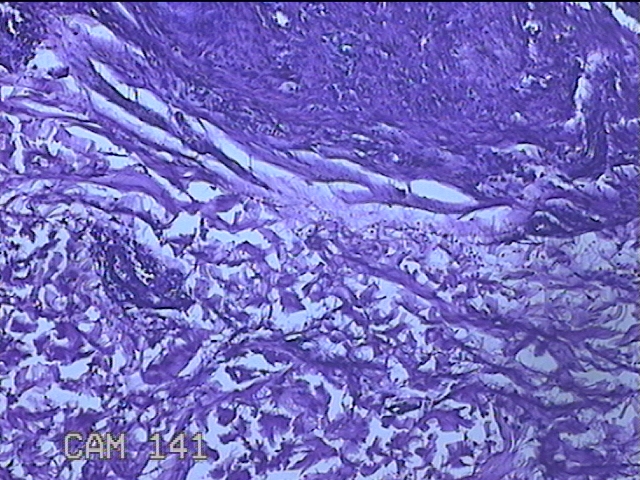

左侧臀部结节

性别

男

年龄

40岁

临床诊断

皮下结节

一般病史

发现左侧臀部结节1年余。

标本名称

大体所见

灰白粉红色组织1.3x0.8x0.3cm一块,表面带梭形皮肤1.3x0.8cm,皮下见结节1.3x1x0.7cm一个,切开结节呈实性,切面灰白粉红色,质软。

图2